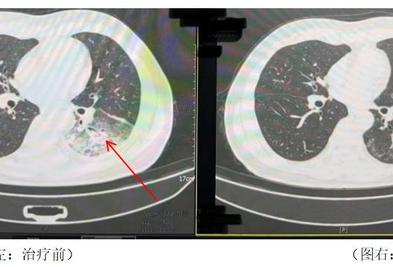

空调一年没开了,专家重要提醒大家。 最近全国很多地方气温逐渐上升,很多人选择开空调乘凉。然而,四川成都市民李先生在开启尘封一年的空调后,意外患上了严重的肺炎,左肺“白”了近一半。是什么情况? 吹3天空调感染军团菌肺炎 这种疾病就像感冒发 2025-05-18